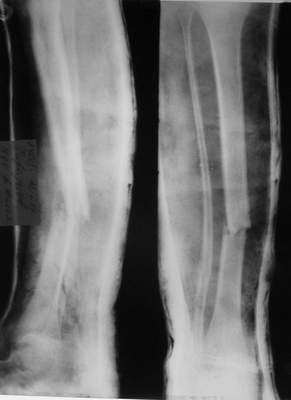

Re: псевдоартроз

A> Так как речь зашла непосредственно о травме, см этапные

A> снимки. Как все было

Встречаются и при переломах голени (б/б с вальгусным смещением).

A> Тем более с такой дугой

См. аттачт.

A> и на этом

A> уровне.